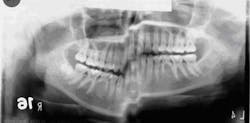

Last month we asked you to Diagnose the X-ray below and send in your answers on what you think the operator may have done wrong. Today we provide you with the image's diagnosis!This month we did not receive a correct diagnosis for the X-ray image problem. Be sure to send in your diagnosis for this month’s Diagnose the X-ray for a chance to win!

X-ray answerThe imaging error was caused by patient movement during exposure; note the step defect in the inferior border mandible. Film exposing and handling tips

- If portions of a panoramic radiograph are blurred and exhibit large steps as seen with the inferior border mandible, the X-ray may need to be retaken.

- Remember that an average panoramic exposure takes approximately 15 seconds.

- Instruct patients about the exposure time so they know what to expect.

- Remind the patient to hold still prior to and during the exposure.